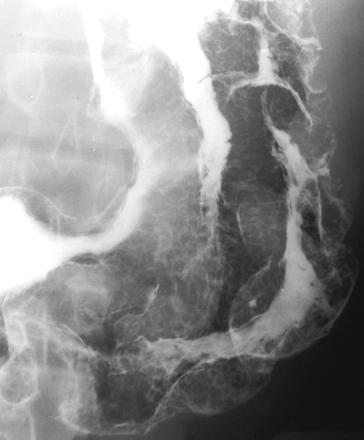

Giant fibroepithelial esophageal polyp